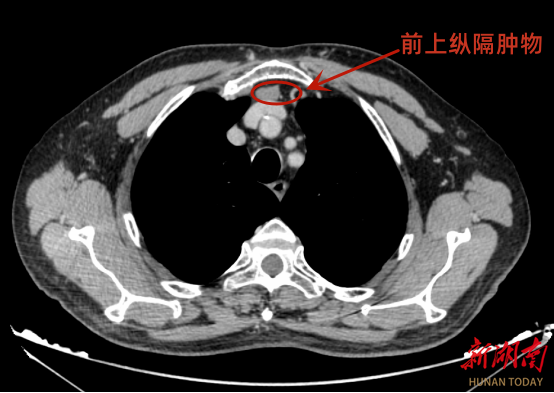

72岁的尹先生(化名)体检时,发现前上纵隔区存在大小约23mm×12mm的肿物,胸部增强CT:均匀轻度强化,随后慕名到该院胸外科就诊。

胸外科首席专家周勇教授接诊后,查看影像资料后发现,其前纵隔肿物紧邻周围血管,加之胸骨后间隙狭小,传统的手术入路视野存在缺陷,手术风险较高。为尽可能确保手术安全,提升术后恢复质量,并实现肿瘤的完整扩大切除,周勇教授组织科室反复评估病情、详细讨论,并与患者及家属充分沟通后,决定行“天平拉钩悬吊胸骨抬高法经剑突下胸腔镜纵隔肿瘤切除术”。